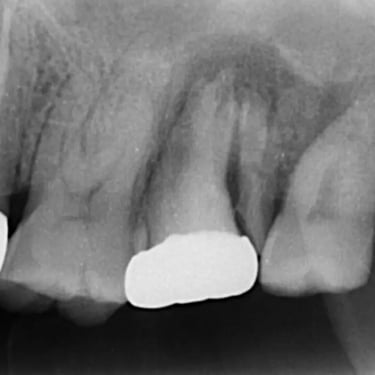

Pulpitis Reversible

La pulpitis reversible es una inflamación leve de la pulpa dental, generalmente causada por caries o una lesión menor.

Los pacientes suelen experimentar sensibilidad al frío o al calor, pero el dolor desaparece rápidamente.

Si se trata adecuadamente, la pulpa puede sanar sin complicaciones. Es importante acudir al dentista para evitar que progrese a una pulpitis irreversible.